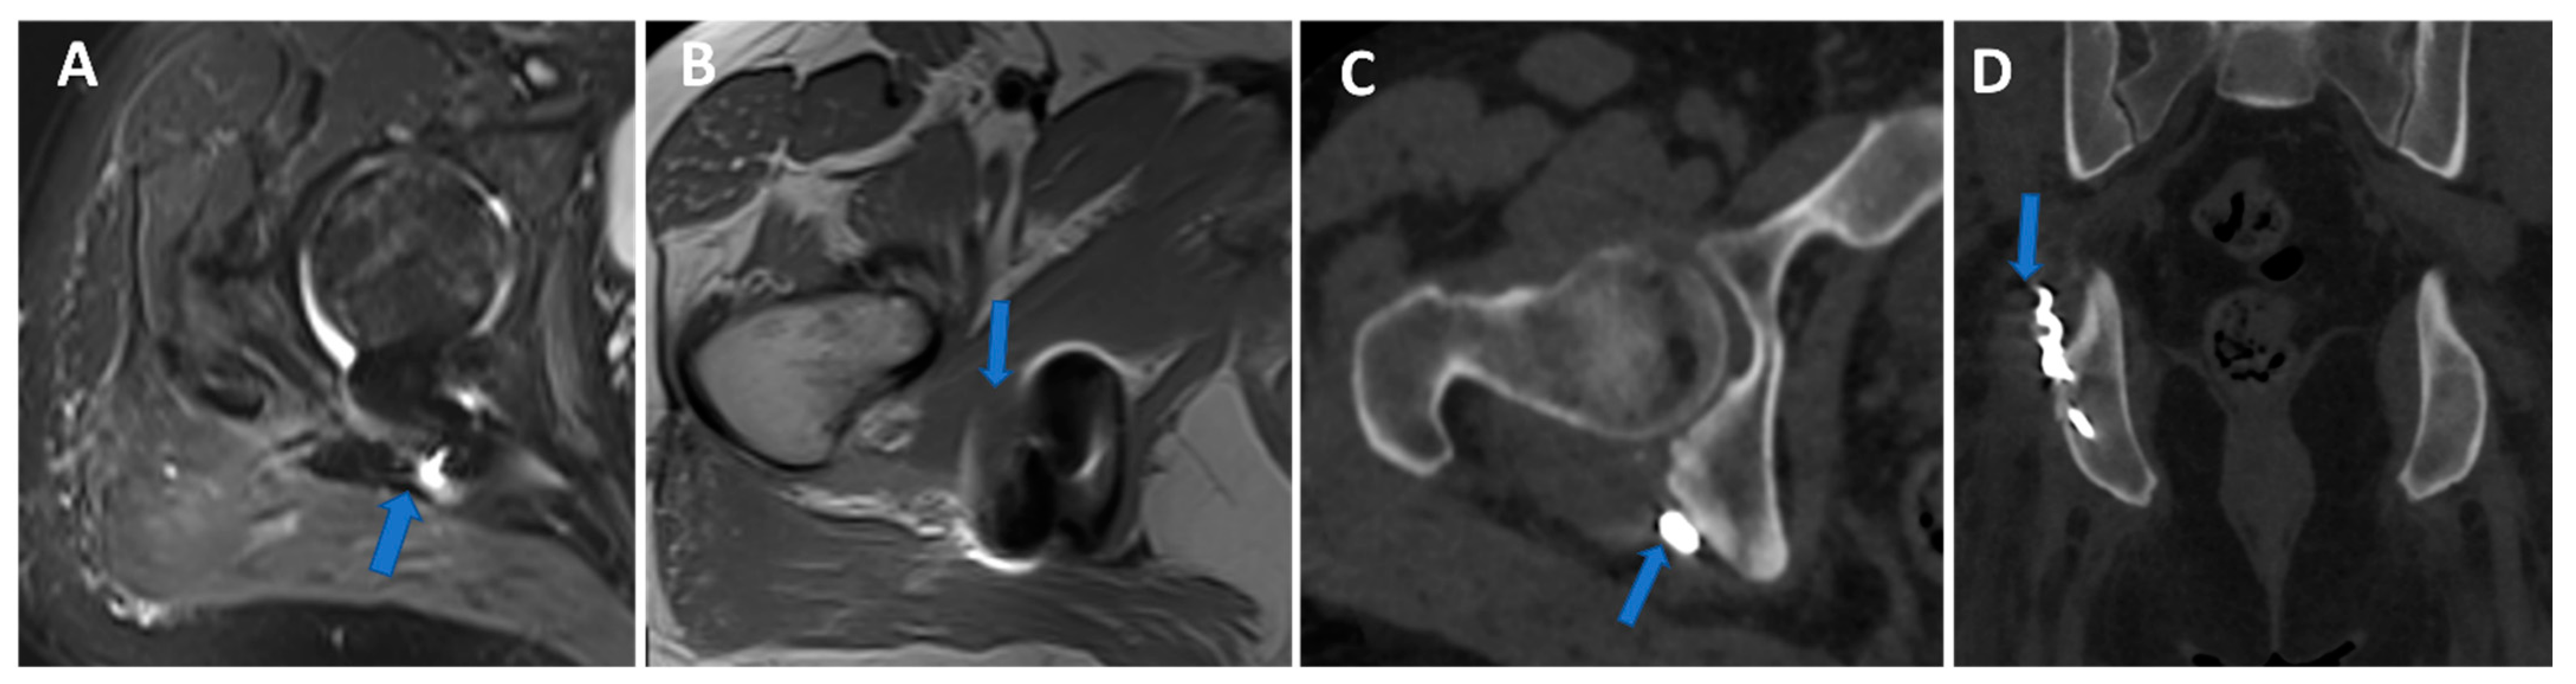

Figure 11.

Persistent hip pain in previous trauma with a surgically treated pelvic fracture. Axial 3 mm STIR and T1 weighted images (A,B) show metallic-induced artifacts around the posterior ischial tuberosity (arrow). On axial and coronal 1 mm VMI reconstructed images (C,D), it is possible to control artifacts and depict the presence of metallic hardware projecting on the course of a thickened right sciatic nerve (arrow).